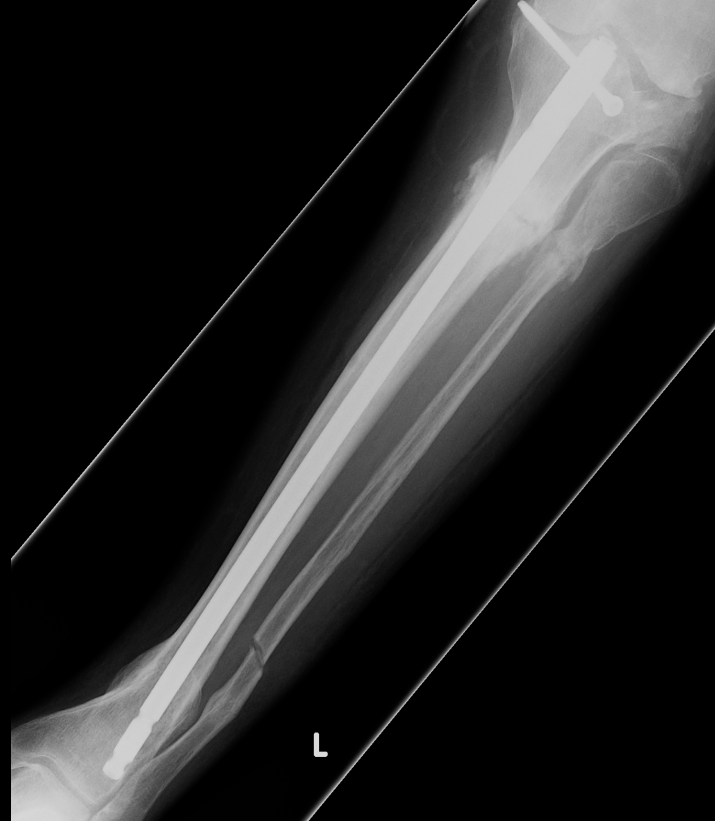

Proximal metaphyseal tibial fracture

Risk of delayed valgus deformity

Acceptable reduction

- varus / valgus < 5o

- anterior / posterior < 5o

- rotation 5o

- shortening 10 mm

Poor remodelling potential

- valgus

- apex posterior angulation / recurvatum

- rotational alignment does not remodel

- shortening / in 2-10 year old average overgrowth is only 5mm